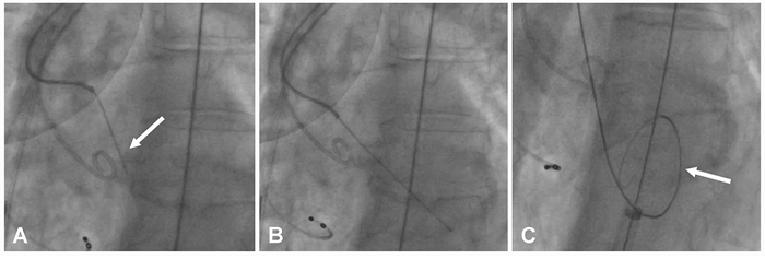

Transcatheter valves are positioned prior to deployment with the aid of aortography, fluoroscopy and, in some instances, transoesophageal echocardiographic guidance. Balloon expandable valves require rapid ventricular pacing (180-220 beats per minute [bpm]) for deployment to reduce cardiac output and avoid inaccurate valve implantation. Other devices may not routinely require ventricular pacing, although this may still be useful in instances when valve positioning is challenging (e.g., horizontal aorta). Figure 2 illustrates implantation of the more commonly used TAVI prostheses.

Figure 2. Mechanisms of deployment of commonly used TAVI devices.

Initial position of the balloon-expandable Edwards SAPIEN 3 valve (A), deployment (B) and final appearance (C). Initial position of the self-expanding Medtronic Evolut R valve (D), deployment (E) and final appearance (F). Appearance of the mechanically deployed Boston Scientific Lotus valve (G), deployment (H) and final appearance (I).